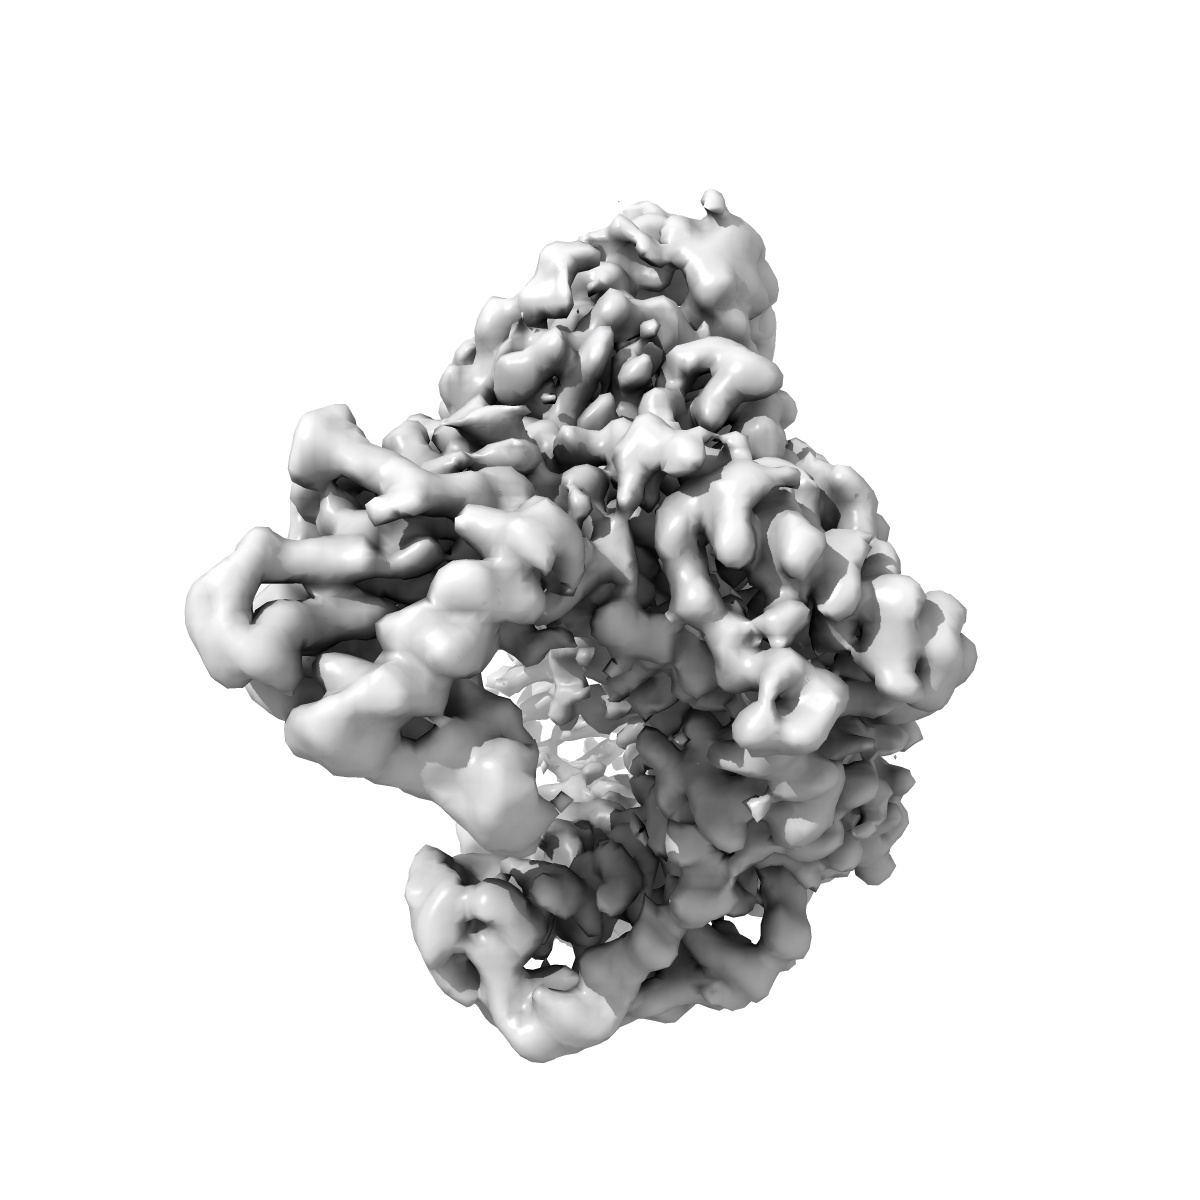

Cryo-EM Structure of HIV-1 Reverse Transcriptase p66 Homodimer in Complex with 5-{2-[2-(2-oxo-4-sulfanylidene-3,4-dihydropyrimidin-1(2H)-yl)ethoxy]phenoxy}naphthalene-2-carbonitrile, a Non-nucleoside Inhibitor, with an Additional Pocket of Density

Single-particle3.09 Å

Fitted models: 9mxs